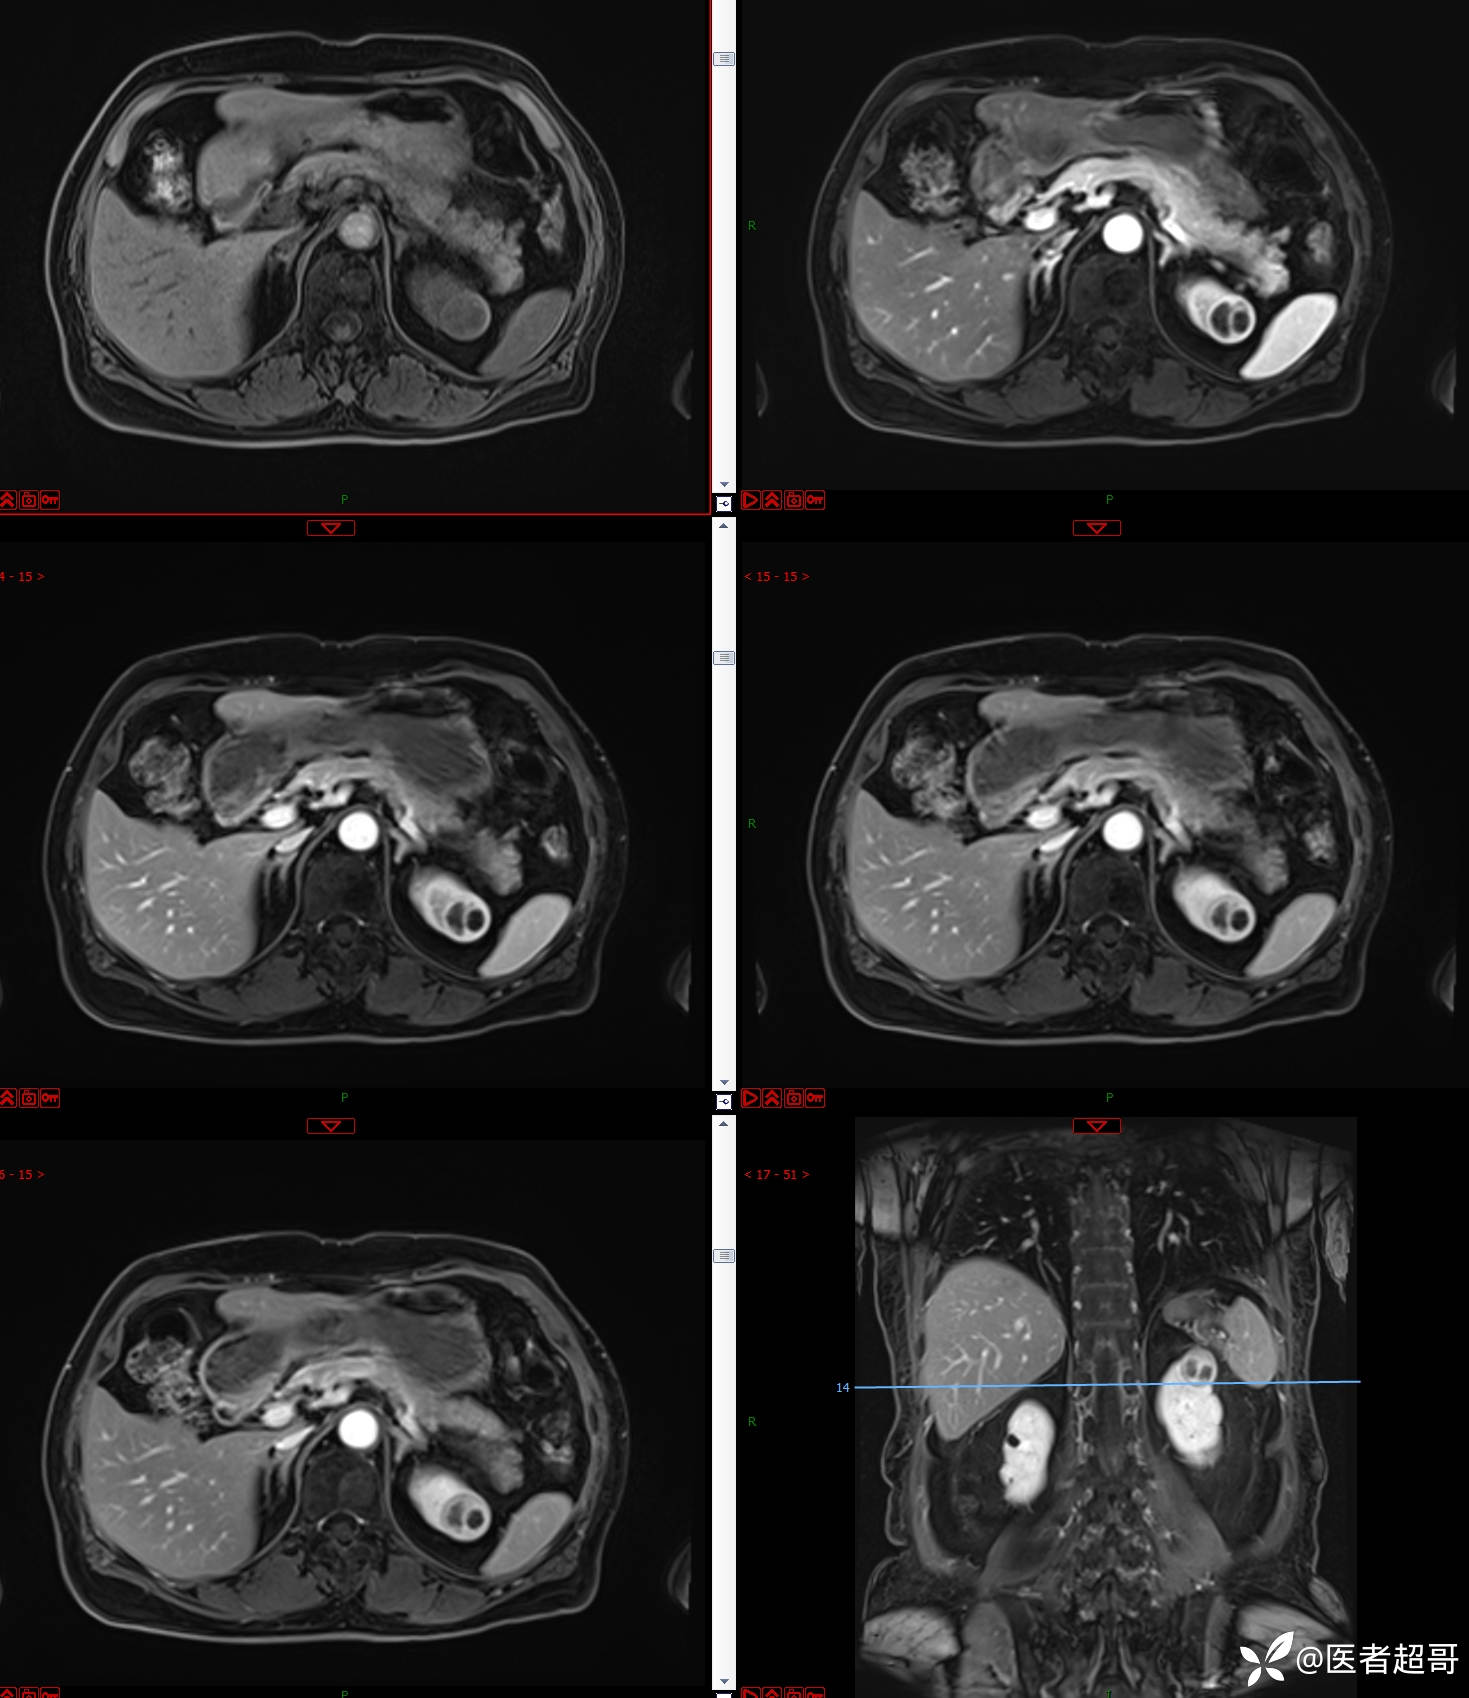

左肾占位2个月就诊,有病理,请分析!

主 诉:查体发现左肾占位2月。

现病史:患者自述2月前于镇中心卫生院行腹部超声发现:左肾实性占位。患者无尿频尿急尿痛,无发热寒战,无恶心呕吐。未行特殊治疗。现患者为求进一步诊治,就诊我院,门诊以“肾肿物”为诊断收入院,患者自发病以来,神志清,精神可,饮食可,睡眠一般,大便正常,体重未见明显改变。